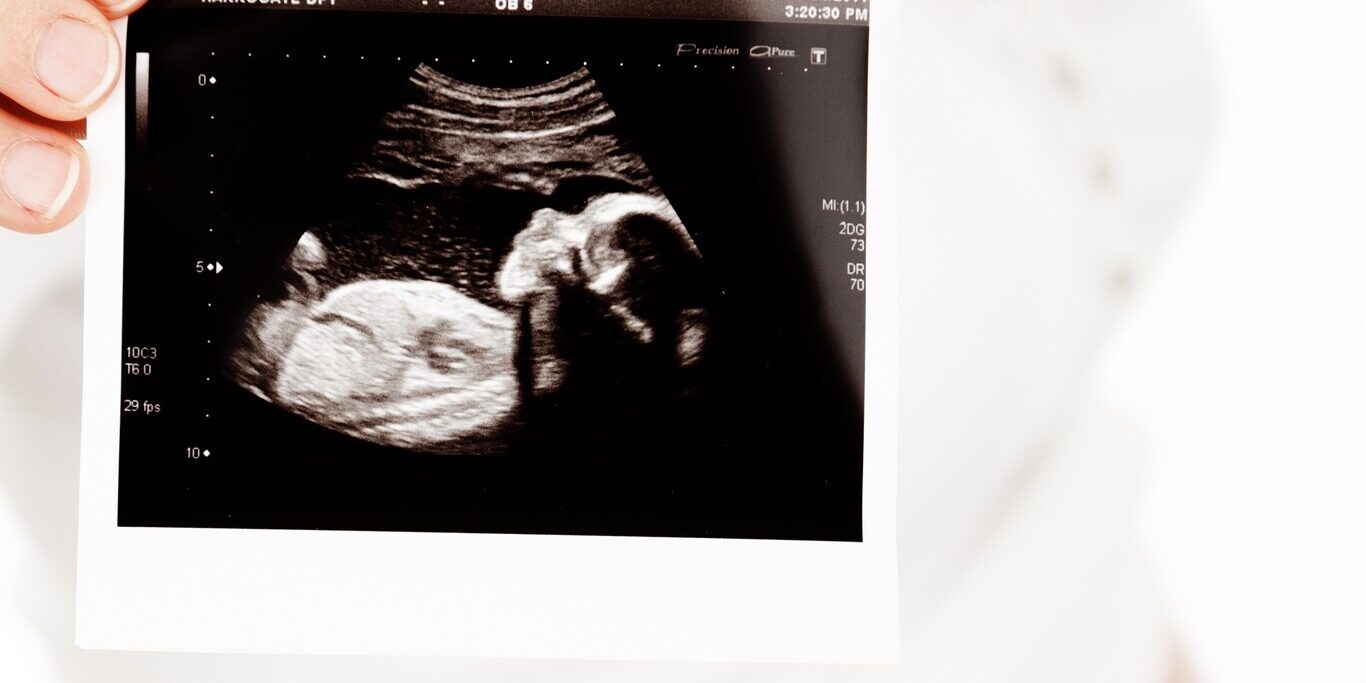

Entre las muchas ecografías que se realizan durante el embarazo, una destaca por su relevancia médica y emocional: la ecografía morfológica de la semana 20. También conocida como “ecografía del segundo trimestre”, esta prueba es clave para valorar el desarrollo del bebé y detectar posibles anomalías. En este artículo te contamos en qué consiste, por qué es tan importante y qué esperar durante la consulta.

Es una ecografía detallada que se realiza, generalmente, entre la semana 20 y la 22 de embarazo. A diferencia de las primeras ecografías, que se centran en confirmar la gestación y estimar la edad del embrión, esta evaluación tiene un propósito mucho más amplio: analizar la anatomía del feto con gran detalle.